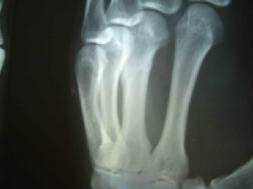

因为剧痛,邢加秋挣脱用手去挡,抬起的手却被犯人李素安抡了一棒,邢眼前一黑晕了过去,不法犯人们又把他打醒,强制他站起来,这时,邢加秋的手背肿得象个馒头,手心青紫,不能动,感觉骨头象断了一样。第二天,犯人李素安、犯人金永军说邢加秋罚站时动摇,对他又一顿毒打,李素安阴险地冲着邢加秋受伤的手砍了一掌,邢大叫一声痛得坐在地上,此后邢家秋的手剧烈疼痛不敢动。(2005年6月在沈阳第一监狱拍的X光片子显示邢加秋左手中指骨折)

这已是两年后的照片了,但仍然清晰可见左手中指骨折的痕迹